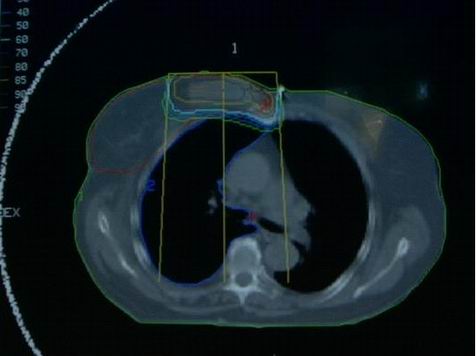

Standard: ozáření celého prsu po parciální mastektomii v dávce 50 Gy za 5 týdnů (2,0 Gy na frakci) s nebo bez ozáření regionálních lymfatických uzlin (obr. 3).

Obr. 3 Technika asymetrických clon při ozařování prsu a svodné lymfatické oblasti